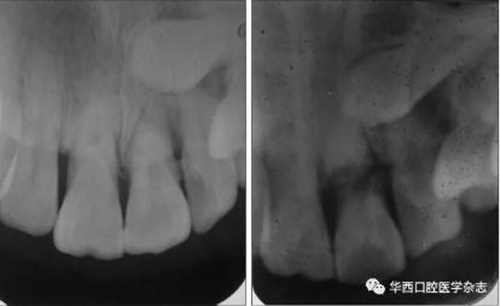

(1)變換角度X線投照的必要性。有些冠根折在行正常角度攝片時不易被發(fā)現(xiàn),變換角度再次攝片則可能被發(fā)現(xiàn)(圖1)。

左:未見根折;右:可見根折。

圖 1 21變換X線投照角度根尖片